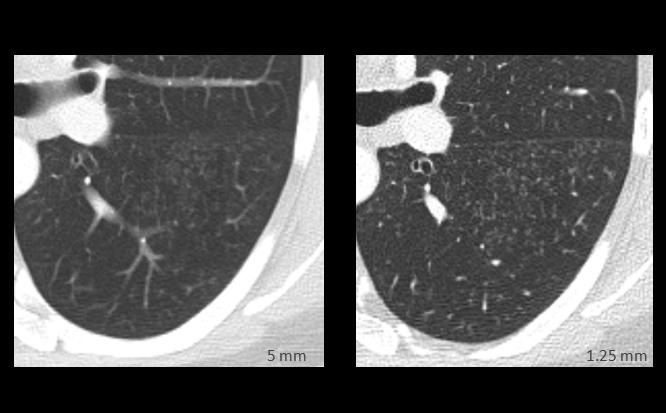

Gallery Sarcoid early Sarcoid

early Sarcoid